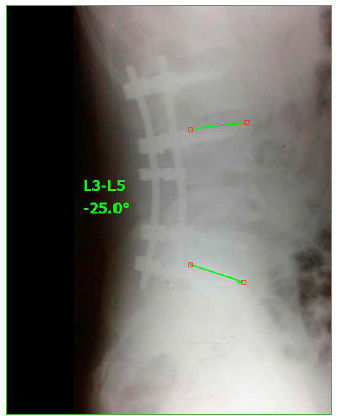

El paciente evoluciona favorablemente, con recuperación neurológica completa. Se corrige la cifosis segmentaria con medición radiográfica a los seis meses de la cirugía adecuada (Cobb L3-L5 25°, lordosis lumbar 39°, incidencia pelviana 40°, IP-LL 1°, inclinación de la pelvis 8°). En la Tabla, se resumen los resultados en función de la clasificación, el puntaje de la ASIA, el porcentaje de ocupación del canal, el porcentaje de colapso vertebral, la cifosis segmentaria L3-L5, la escala analógica visual a los seis meses de la cirugía y el índice de Oswestry a los seis meses.

En ambos casos presentados, los pacientes sufren el trauma secundario a la caída hacia atrás del binomio caballo- jinete, durante el “voleo” del animal, el caballo cae sobre su dorso aprisionando al jinete contra el suelo. El jinete queda atascado entre la cabalgadura y el suelo con la región lumbopelviana en máxima flexión hacia el zenit; de esta forma, recibe el peso del animal sobre los isquiones y el sacro. El paciente en posición de hiperflexión permanece fijo con el platillo vertebral superior de S1 paralelo al suelo (Figuras 13 y 14), la pelvis y el sacro actúan como un verdadero “impactor” que resume las fuerzas del peso del caballo y su caída en la columna lumbar baja con la consiguiente fractura de tipo estallido de la cuarta vértebra lumbar.

Figura 13.

Valoración radiográfica del mecanismo de lesión.